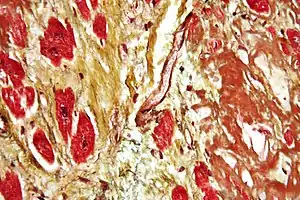

| Micrograph of a heart showing fibrosis (yellow – left of image) and amyloid deposition (brown – right of image). Stained using Movat's stain. | |